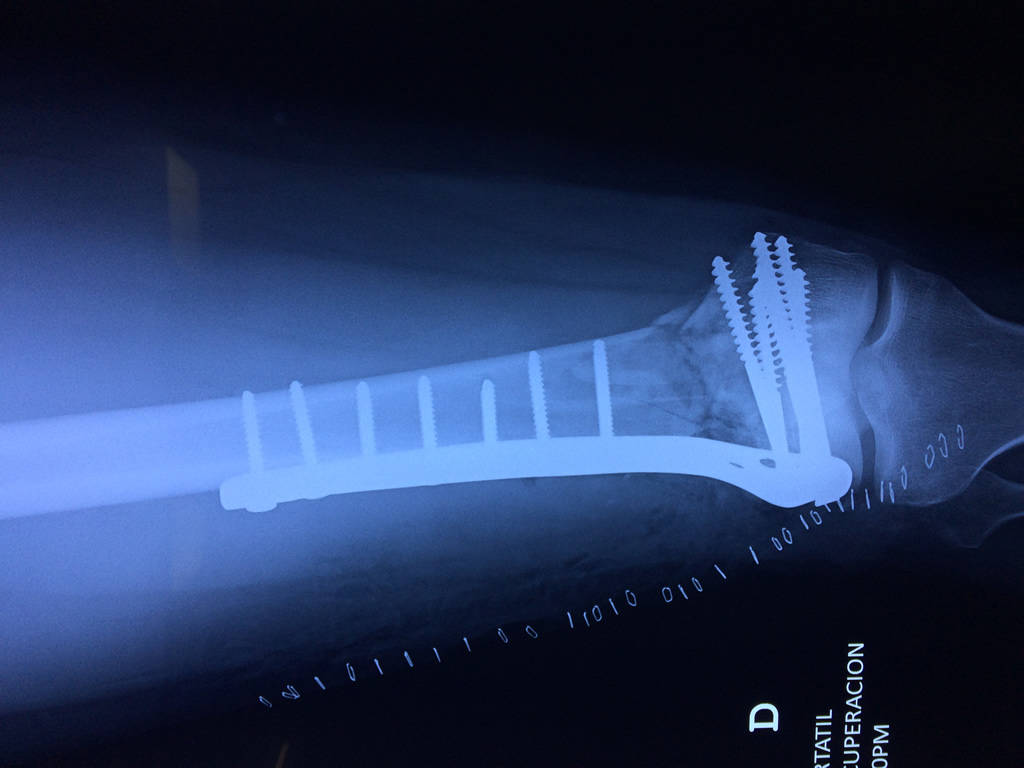

Cirugía de Rodillas

El fémur es el hueso del muslo, el segundo segmento del miembro inferior. Es el hueso más largo, fuerte y voluminoso del cuerpo humano.